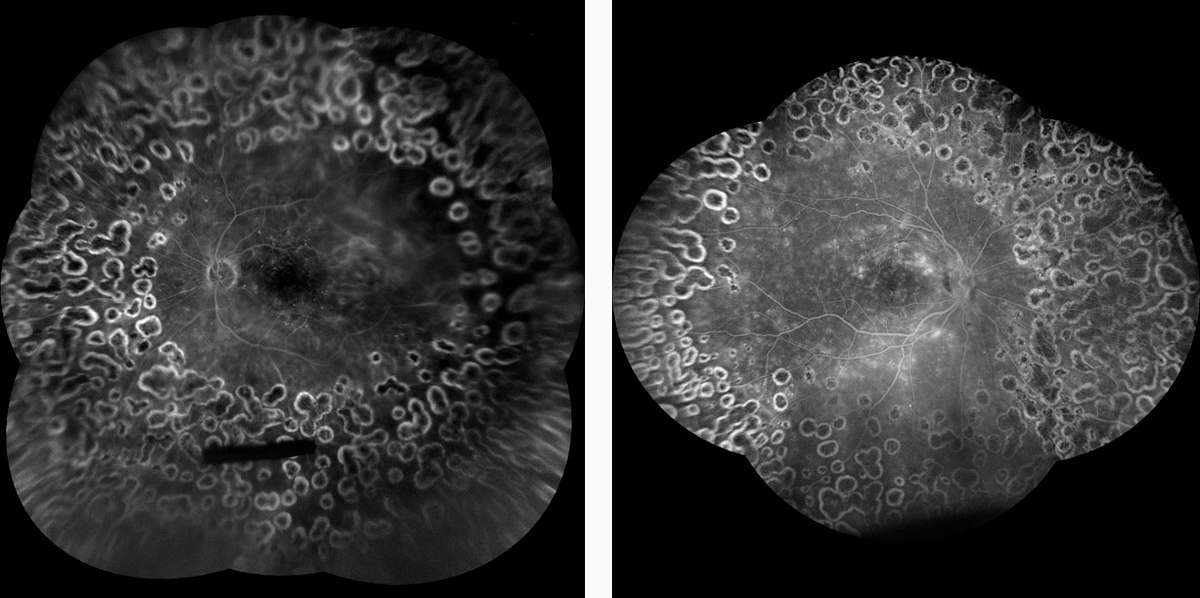

iCare EIDON FA es un sistema de imagen de alta gama que combina lo mejor de la tecnología iCare EIDON con la capacidad automatizada de angiografía con fluoresceína para ofrecer una gama completa de modalidades de imagen con una calidad inigualable. Ofrece imágenes de campo amplio del fondo de ojo mediante fluorangiografía, conservando la calidad, la nitidez y los detalles de la imagen, incluso en la periferia.

iCare EIDON FA también ofrece la ventaja adicional de capturar una grabación de video detallada de fluorangiografía (FA) de ultra alta resolución, que proporciona una visión realista y dinámica de la vasculatura retiniana y los mecanismos circulatorios que podrían pasarse por alto con la fotografía estática con flash.

Además, gracias al módulo de campo ultra amplio EIDON, es posible ampliar el campo de visión hasta 200°, lo que ayuda a detectar signos de patologías que comienzan a aparecer en la periferia. El módulo de campo ultra amplio permite una visión de la retina desde 120° con una sola toma hasta, 200° con la función Mosaic (mosaico).